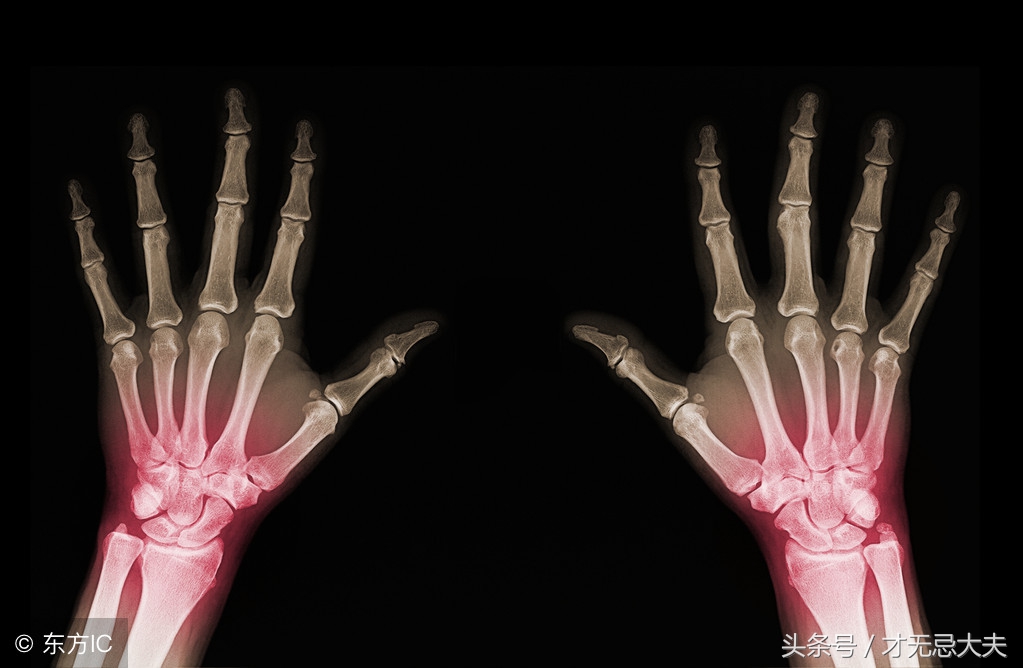

类风湿性关节类是以侵蚀性、对称性多关节炎为主要临床表现的慢性、全身性、自身免疫性疾病。

患者可以出现关节晨僵、关节肿痛、关节畸形。

X线平片:关节腔破坏等。